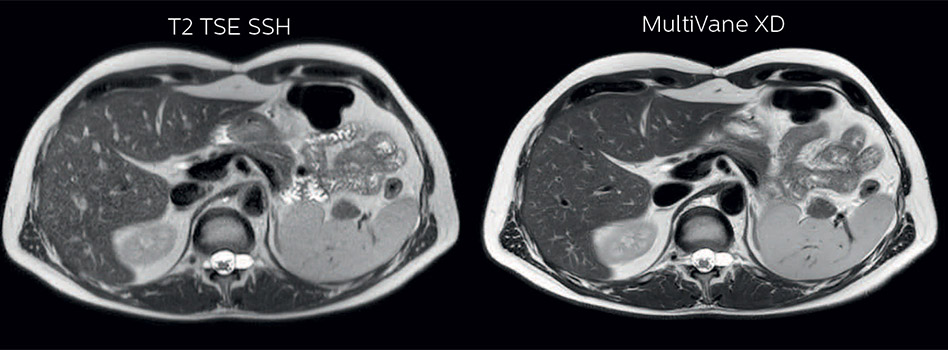

Comparison of liver MRI with and without MultiVane XD motion correction

In this example the image quality of the MultiVane XD images is evidently better than in the images without MultiVane XD. Ingenia 1.5T with dS Torso coil solution.